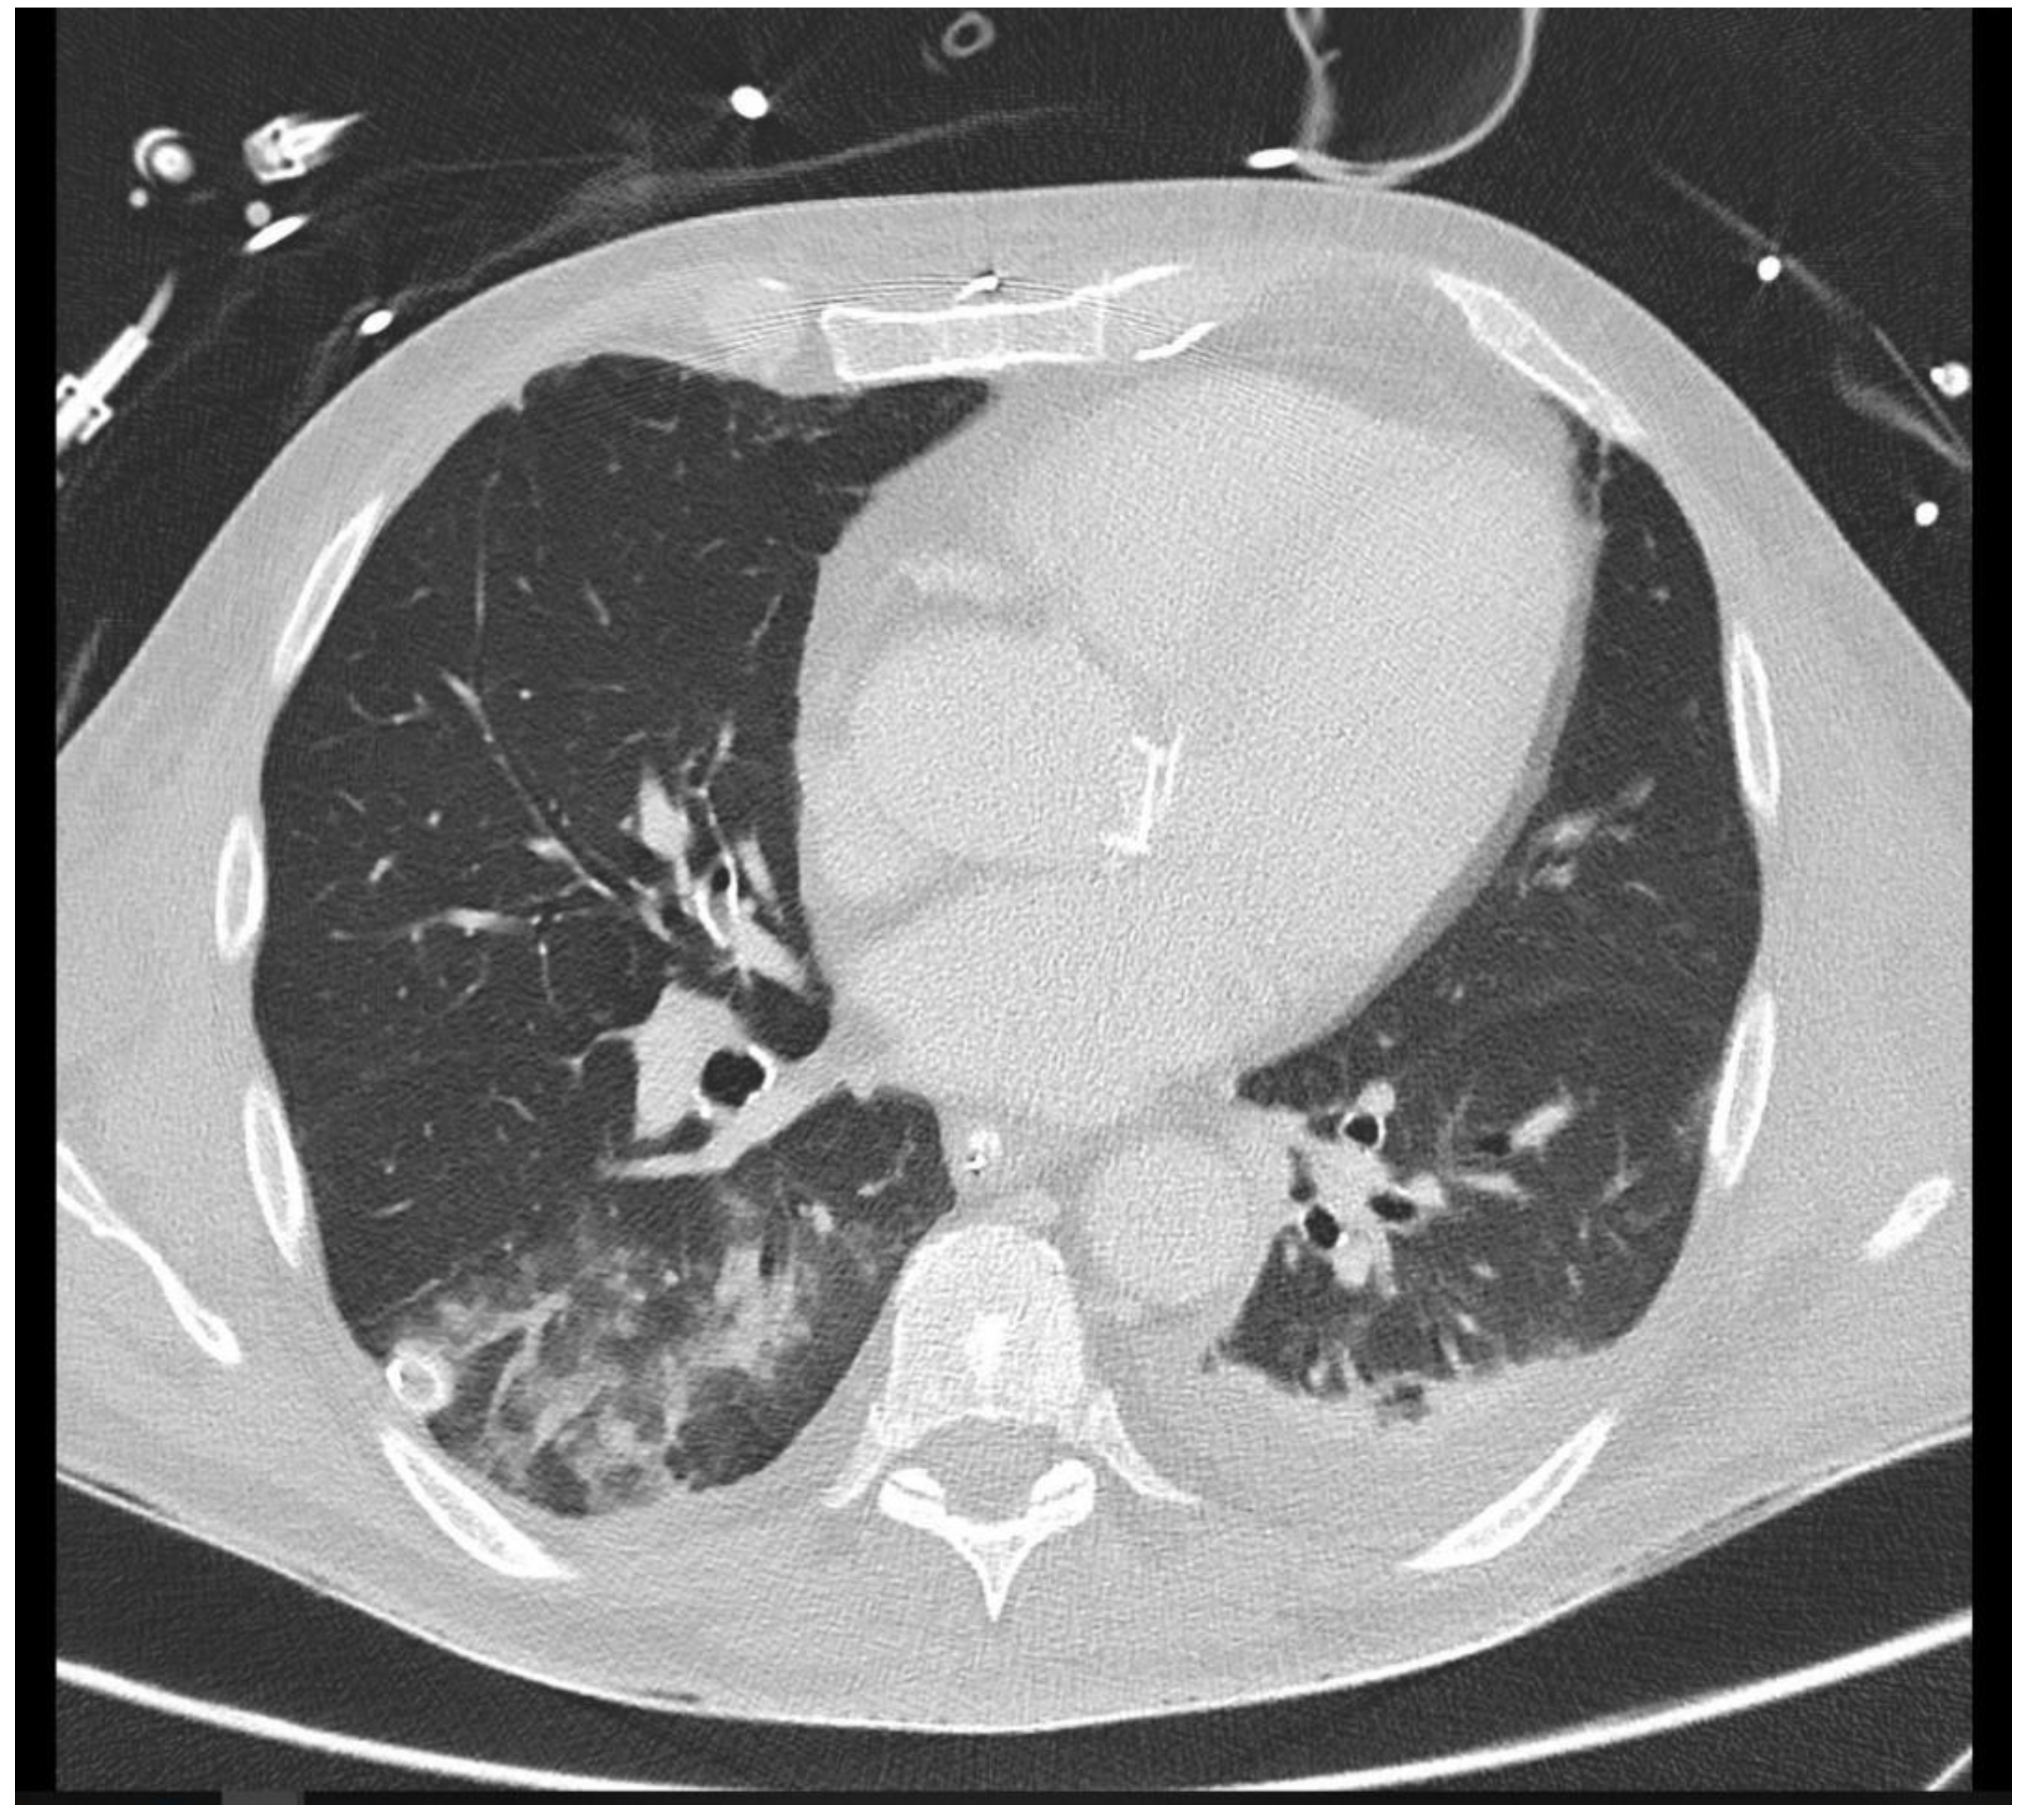

The distribution of thoracic foci was concentrated primarily in three areas: the lungs, mediastinum, and sternum. Of the thoracic findings, 90 foci were present in the lungs, representing 97.8% of the total, while the mediastinum and sternum each contained one focus (refer to Table 3). Pulmonary foci demonstrated high diagnostic conclusiveness, with 75.6% definitively diagnosed. This highlights the effectiveness of CT imaging in accurately detecting and characterizing lung-associated inflammatory processes, as exemplified in Figure 3.

Figure 3. A 26-year-old intensive care patient with elevated inflammatory markers. Typical morphologic signs of pneumonia in the right lower lobe are evident, including ground-glass opacity (GGO), bronchial wall thickening, and pleural effusion.